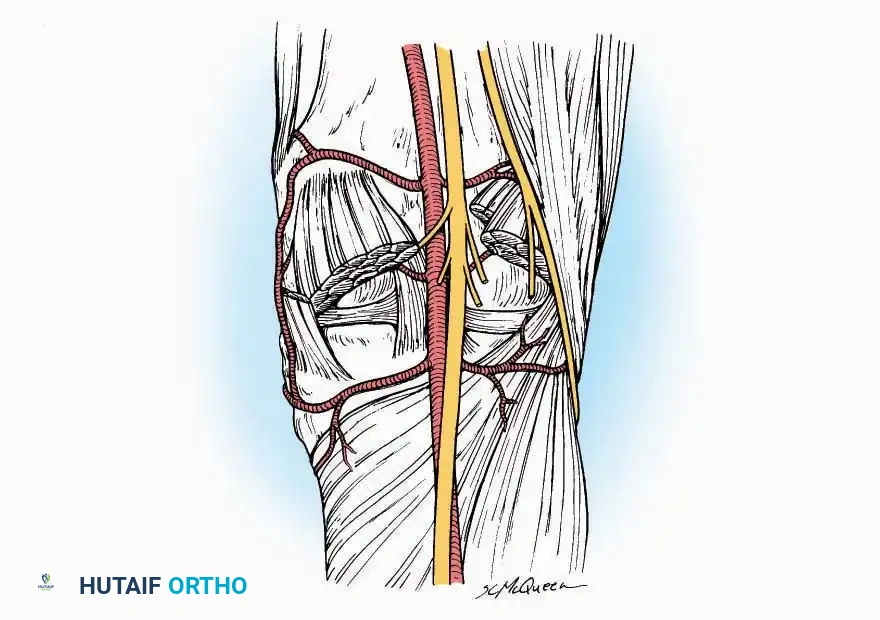

* Vascular Ligation: This trajectory usually requires the identification and ligation of the anterolateral malleolar and lateral tarsal arteries.

* Deep Exposure: Retract the extensor digitorum longus (EDL) tendons, the dorsalis pedis artery, and the deep peroneal nerve (DPN) medially. Incise the anterior ankle capsule to expose the tibiotalar joint.

* Neurovascular Bundle: Incise the extensor retinaculum. Carefully identify the anterior tibial artery and the deep peroneal nerve, which typically lie between the EHL and EDL, or directly deep to the EHL. Retract the neurovascular bundle laterally with the EDL, or medially with the EHL, depending on the specific anatomical variant encountered (lateral retraction is most common).